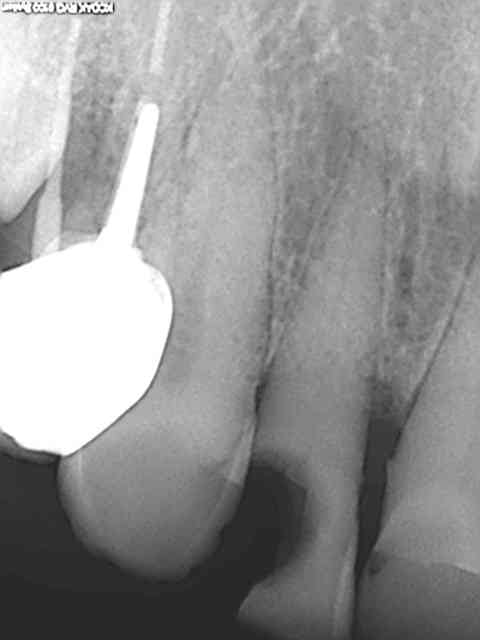

Faut pas pousser. Ce matin patient RDV 11h30 et sorti 12H05, Status radio (on ne sait jamais pas venu depuis 2009) endo, empreinte, provisoire incluses. Un peu énervé par le lapin d'une heure plus tot dans la matinée !

Ouais mais vu la rétraction pulpaire une reconstitution pré endo aurait quelque peu obscurci le champ opératoire, je rase pour y voir plus clair.